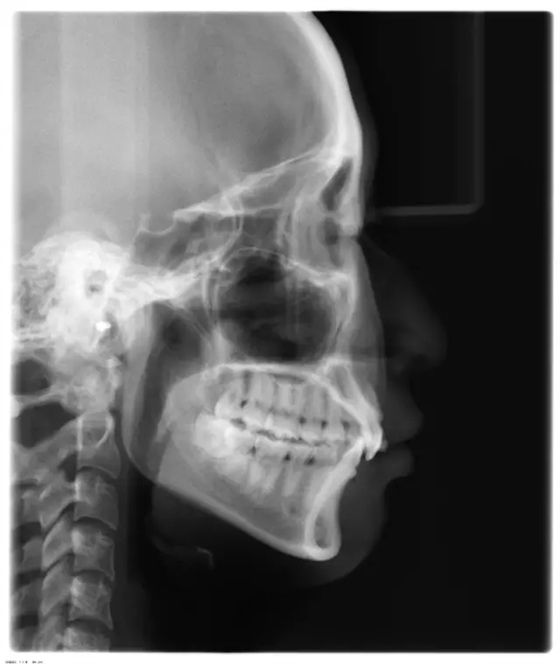

患者側(cè)面凸,鼻唇角較銳,笑時(shí)露齦笑明顯上下牙列擁擠,磨牙尖牙Ⅱ 類關(guān)系,3 度的深覆牙合,上頜中切牙伸長內(nèi)傾拔除上頜雙側(cè)的第一前磨牙,先粘上頜高轉(zhuǎn)矩的自鎖托槽排齊牙列,唇向開展上頜切牙,有一定的覆蓋,粘下頜標(biāo)準(zhǔn)轉(zhuǎn)矩托槽,上頜 1, 2 之間植入種植支抗壓入,同時(shí)后牙 5, 6 之間植入種植支抗內(nèi)收前牙,打開咬合關(guān)閉間隙。治療關(guān)鍵:前牙轉(zhuǎn)矩的控制第 1 個(gè)月 上頜粘上 Damon Q 高轉(zhuǎn)矩托槽,上 .014 熱激活 NiTi 絲。第 3 個(gè)月 上換 .014 x .025 熱激活 NiTi 絲。第 5 個(gè)月 上頜基本排齊,覆蓋增大,上換 .017 x .025 NiTi絲,下頜粘托槽,下 .014 熱激活 NiTi 絲。第 7 個(gè)月 上 .017 x .025 NiTi 絲加搖椅,下?lián)Q .014 x .025 熱激活 NiTi 絲第 9 個(gè)月 上頜換 .019 x .025 NiTi 絲加搖椅,下頜換 .017 x .025 NiTi 絲第 11 個(gè)月 下頜換 .019 x .025 加搖椅,上頜 1, 2 之間, 5, 6 之間植入種植釘,下頜出現(xiàn)散隙。第 13 個(gè)月 上頜換 .019 x .025ss 加搖椅,前牙種植釘用 Power Chain 壓低前牙(每側(cè) 100g),后牙種植釘關(guān)閉間隙(每側(cè) 150g),下?lián)Q .019 x .025ss,Power Chain 關(guān)閉間隙。第 19 個(gè)月 上頜前牙基本壓低到位去除前牙種植釘,繼續(xù)用關(guān)閉間隙,下頜散隙關(guān)閉。

第 22 個(gè)月 上頜覆蓋變小,去除 5, 6 之間種植釘,后牙前移關(guān)閉間隙。第 30 個(gè)月 患者未配合中線牽引,下中線仍有 1mm 右偏,患者對矯治效果滿意要求拆除,拆除固定矯治器,取模制作壓模保持器。 1.骨性 Ⅱ 類的患者內(nèi)收前牙時(shí)需對上頜前牙的轉(zhuǎn)矩進(jìn)行較好的控制才能獲得良好的面型和唇部形態(tài)。 2.露齦笑的患者治療前要分析其病因是唇、牙齦、牙齒、牙槽骨、上頜骨或多種因素結(jié)合,再制定矯治方案。 3.Ⅱ 類第二分類伴露齦笑的患者的上頜前牙移動軌跡是唇向開展-壓低-整體內(nèi)收。 4.Ⅱ 類第二分類牙齒舌傾比較厲害的情況,上頜中切牙慎用樹脂咬合墊。 5.壓低前牙或控根移動時(shí)容易發(fā)生牙根的吸收,需輕力緩慢的移動。